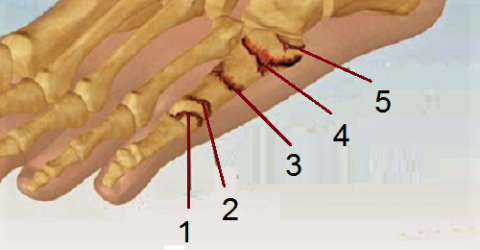

Перелом сесамовидной кости: Визуализация травмы и её лечение